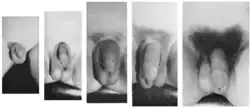

![]() Etapele dezvoltării organelor genitale ale bărbatului în timpul pubertății | |